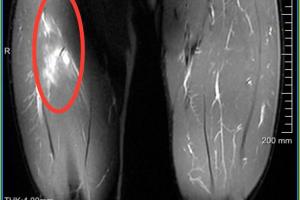

范双杰,4.25日主场对阵河南俱乐部酒祖杜康的比赛中,球员上半场比赛中左大腿受伤。伤后经核磁共振检查,显示左大腿缝匠肌肌腱拉伤,左大腿股直肌股外侧肌拉伤Ⅱ°。

目前症状:左大腿抬高疼痛4级(0-10)、行走痛4级、跑跳疼痛6-7级,髋膝关节灵活度优其他正常。

治疗方案:急性期对球员采取冷疗措施,24小时后进行激光、微波、热透、针灸等治疗;同时进行非疼痛下强化核心稳定性力量训练

评估伤期:2周左右